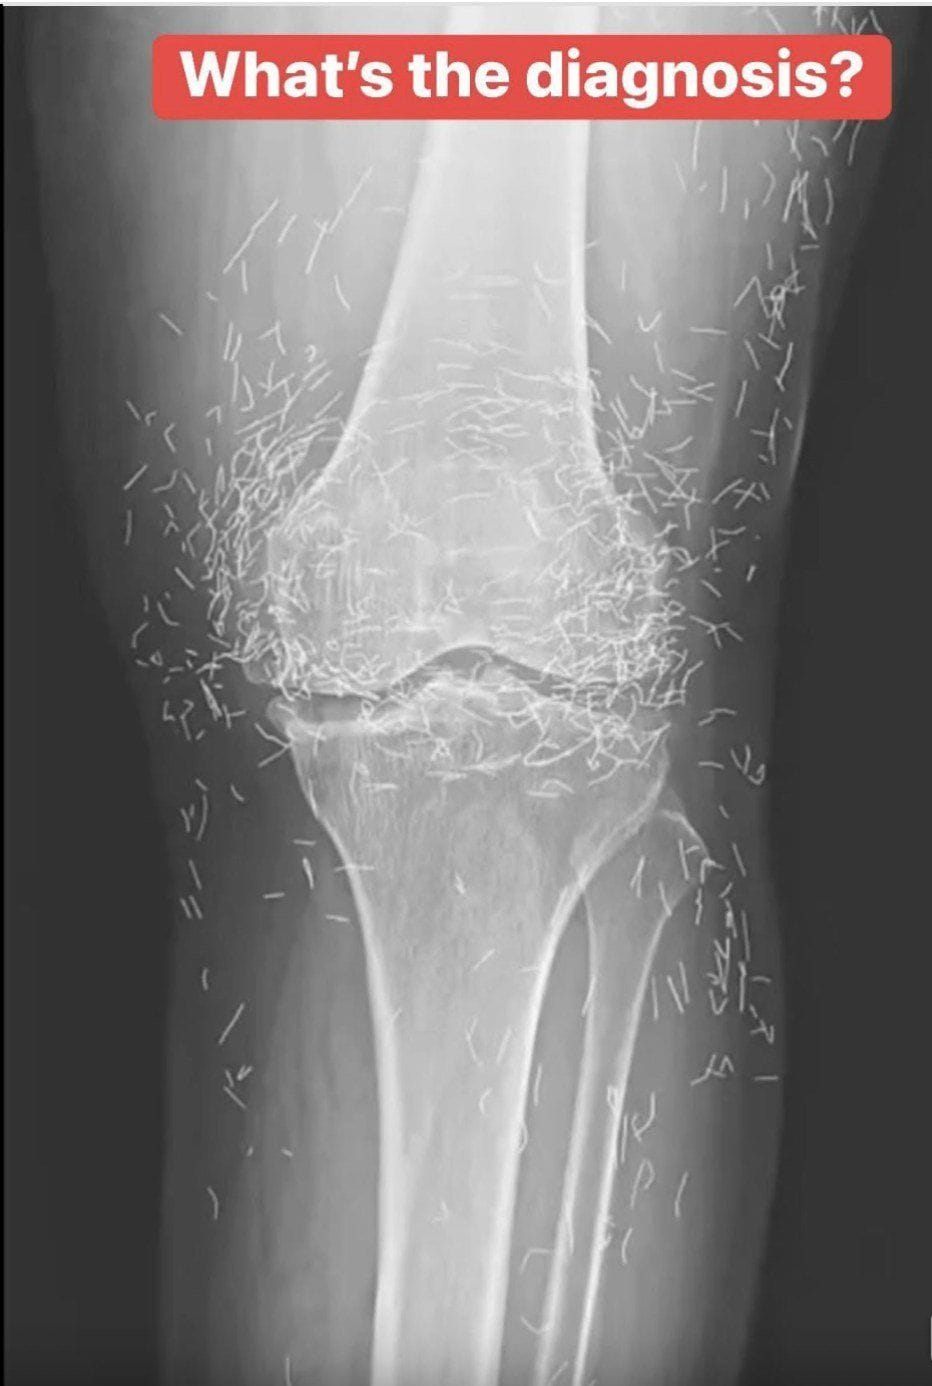

Years later, when doctors took X-rays to evaluate her knee condition, they weren’t prepared for what appeared on the images. Her knees were filled with dozens of bright, metallic flecks — tiny needles embedded deep within the joint area.

The findings were later documented in a case published by the New England Journal of Medicine.

Beyond inflammation, the needles created another problem: imaging complications. Metal objects can obscure parts of the anatomy on X-rays, making it harder for doctors to clearly assess joint damage or disease progression.

Even more concerning, the presence of metal inside the body can make certain scans dangerous. MRI machines rely on powerful magnetic fields, and embedded needles may shift during scanning, potentially damaging blood vessels or surrounding tissue. In short, future diagnostic options for this patient became limited.